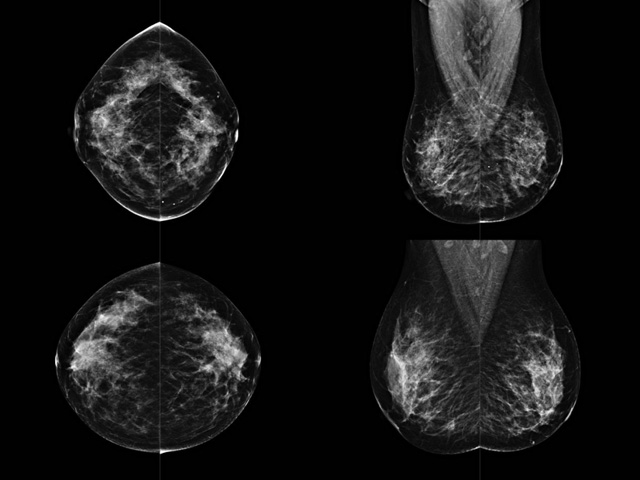

乳房檢查時(shí)候要注意一些細(xì)節(jié),需要更深入的了解這樣才能使檢查更準(zhǔn)確。乳腺DR是乳腺癌的篩查診斷工具設(shè)備。是乳房方面檢查的重要影像方法。它可以臨床檢查出早期的乳腺癌??梢耘袛嗔夹詯盒浴R?yàn)樗梢詸z查出早期的病變。對(duì)良性惡性檢查的準(zhǔn)確率達(dá)到90%以上。發(fā)病高峰年齡為45歲到54歲。50歲檢查出來乳腺癌病患,可以讓死亡率下降3成。所以30-40歲女性每年做一次乳腺DR檢查。40歲以上就一年兩次。如果家族史有乳腺癌的30歲以下也需要做檢查。清晰顯示乳腺各層組織嚴(yán)重的乳腺增生,乳腺炎,乳腺外傷也建議1年檢查一次。極大提高了早期乳腺癌的敏感度和診斷率。

大角度、高質(zhì)量的乳腺檢查,可以讓女性帶來身體健康安全。為醫(yī)生提供了高清影像數(shù)據(jù)。乳腺檢查時(shí)候各個(gè)部位影像顯示出來。白色乳腺導(dǎo)管跟纖維結(jié)締組織。模糊的是脂肪。病變一般是不透明的白色。有需要放大來檢查。乳腺DR沒有重疊偽影。輻射劑量更少。因?yàn)槿橄侔┌l(fā)病每年都有所提高,對(duì)女性都造成了嚴(yán)重的身體健康危害。早做檢查早治療是不可忽視的舉措??梢源蟠蟮慕档?/span>死亡率。保證身體健康。一般檢查避開經(jīng)期,來完7天左右是最佳的檢查時(shí)間。絕經(jīng)的女性就沒有要求。孕婦不參加乳腺DR檢查, 6個(gè)月內(nèi)準(zhǔn)備妊娠的婦女也不宜行此檢查。